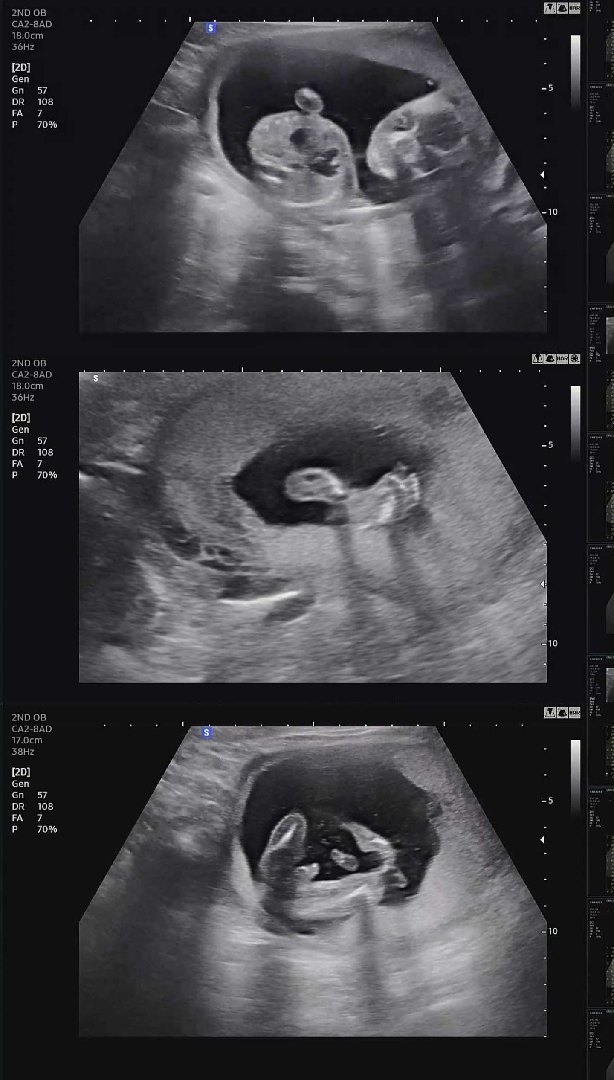

17주5일차 용용이(아들) 초음파♥︎

17주5일차 2차 기형아검사 하면서 보고온 용용이 초음파에요 ㅎㅎ 얼굴,발바닥,🌶 까지 잘 보고 왔어요 :) 주수에 맞게 잘 크고 있는 모습이 너무너무 기특하네요 얼른 태동도 느껴보고 싶어요